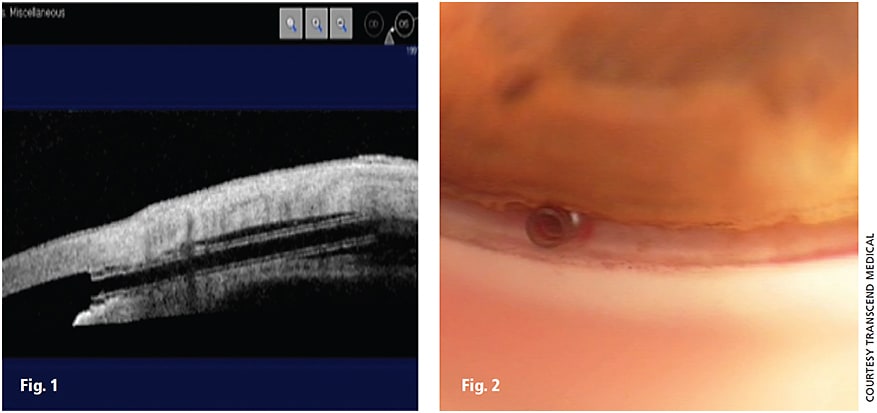

Figure 1. UBM of the CyPass in the angle.

Figure 2. The CyPass in the angle after implantation.